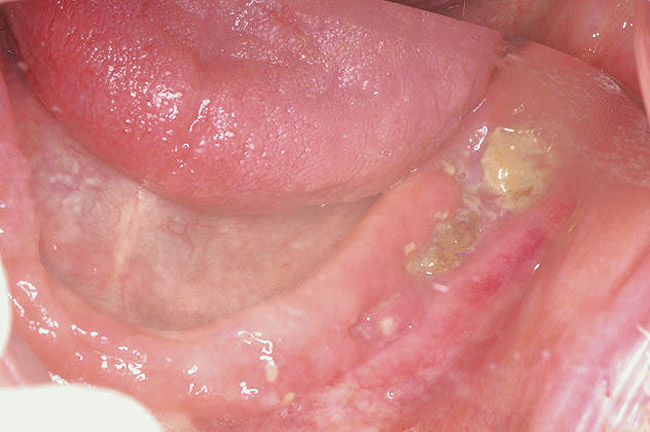

Figure 19  Infection seen after the biopsy.

Figure 19

As stated earlier, spontaneous osteonecrosis is also possible. Figure 14 shows a case of spontaneous BRONJ resulting from wearing an ill-fitting denture. The patient had noticed the foreign material, but chose not to act on it. When the material was removed in the dental office (Figure 15 and Figure 16), blood streamed from the nose, so severely that the patient had to be sent to an ear, nose, and throat (ENT) physician. The ENT took a computed tomography scan, which showed a large radiolucency in the upper left quadrant where the foreign material once had been (Figure 17). A review of the radiograph (Figure 18) showed that bone in the maxillary arch had decreased mineral density compared with the mandible. The biopsy report found necrotic bone with organisms consistent with actinomyces. These findings were consistent with biopsies found in the literature.22 When the patient returned for a 1-week follow-up, she still had signs of infection and the site had a foul odor and a discharge (Figure 19). The patient was informed that she should follow up with the ENT and return to the dental office after the infection had been resolved.